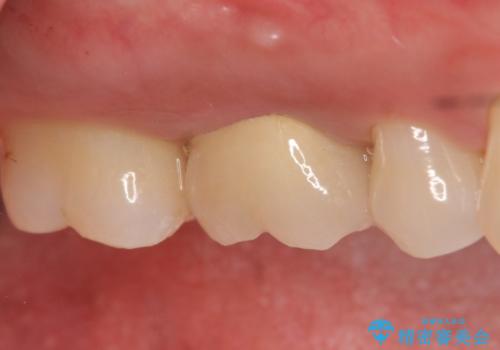

古い樹脂やカリエスを除去後、形を整え、オールセラミッククラウンによる補綴を行いました。

今回用いたオールセラミッククラウンはジルコニアフレームという白い素材の上にセラミックを盛っているため、審美性が非常に高いのが特徴です。

また、ジルコニアは人工ダイヤモンドの材料にも使われているほど高い強度を持っており、そのためオールセラミッククラウンは審美性だけでなく、奥歯やブリッジの補綴も可能とするクラウンです。